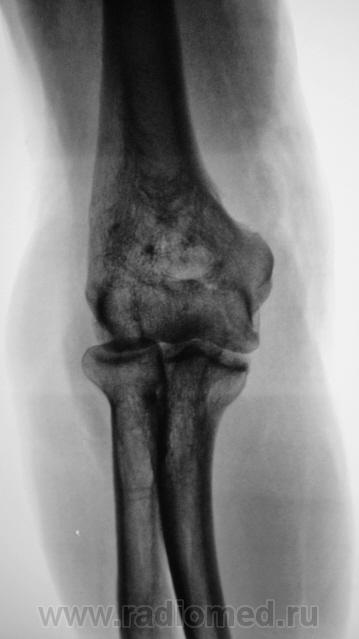

Пациент направлен на рентгенографию локтевого сустава. Была травма или не была не помнит. Пациент весьма пьющий, направлен хирургом с диагнозом "перелом". Рука в локтевом суставе полность не разгибается.

Ваше мнение уважаемые коллеги?

Наверно, застарелый перелом в области блока плечевой кости. Не понятен периостит.